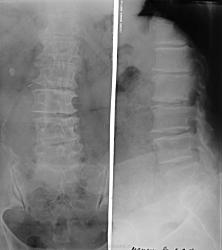

Поясничный лордоз выпрямлен.Снижена высота всех межпозвонковых дисков.Субхондральный склероз замыкательных пластинок тел позвонков, краевые остеофиты.Сужение суставных крестцово-повздошных суставов.В проекции правой почки плотная тень округлой формы с четкими ровными контурами, подозрительная на конкремент.Справа на уровне 3-5 позвонков краевое скорлупообразное обызвествление ( чего-то). Остеожондроз пояснично-крестцового отдела позвоночника.Спондилез тел позвонков.МКБ.Конкремент правлй почки( желчного пузыря?).Обызвествленное образование брюшной полости? Обызвествленная аневризма брюшной аорты?Чувствую, что что-то упустила.Каюсь.Жду результатов с нетерпением.

недавно на сайте был случай подозревали конкременты в правом мочеточнике, но расположение было несколько иное, случай закончился итогом-обызвестлением аневризмы аорты, похоже и тут.

да конечно есть аневризма брюшной аорты, случай вчерашний.. я как увидел аж обрадовался, ну думаю если бы на сайте недавно не демонстрировался схожий случай мог бы и пропустить... Пациентка знает о аневризме, но мне не сказала... может проверяла?(она бывший врач), хотя термин бывший навряд ли уместен, обещала принести КТ - выложу Ну и естественно есть, любимый теперь и мной, ваккум феномен практически всех дисков..

P.S а тень подозрительная на конкремент - артефакт)))